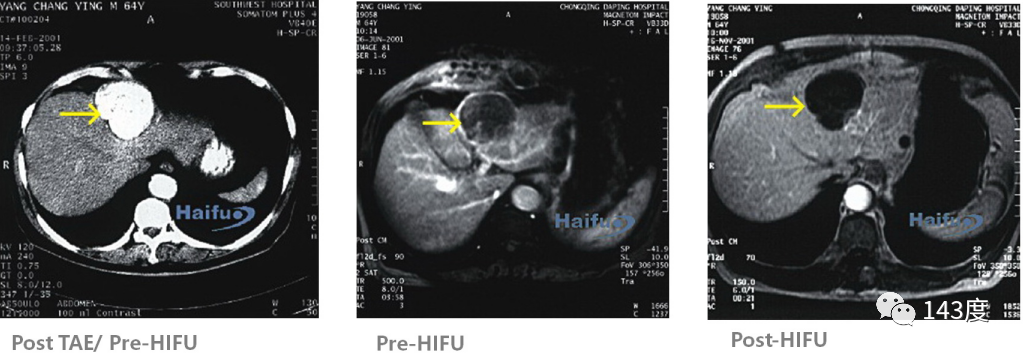

Liver Cancer Treatment Case 5:

Patient: Male, 70 years old, primary liver cancer

Residual tumor observed on MRI after iodine oil deposition following transarterial embolization. Patchy enhancement disappeared after HIFU treatment, indicating complete tumor ablation.